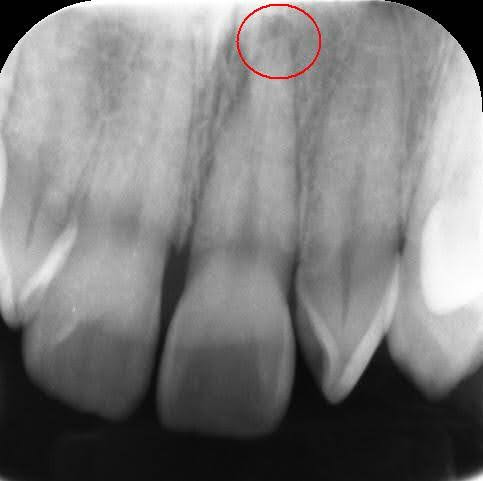

Dr.:歯の神経(歯髄)は、強打の為断絶してしまい、助かりません。かといって抜歯はしません。壊死してしまった根管内の歯髄を綺麗にする根管治療をします。

赤丸が膿んでいる病変部